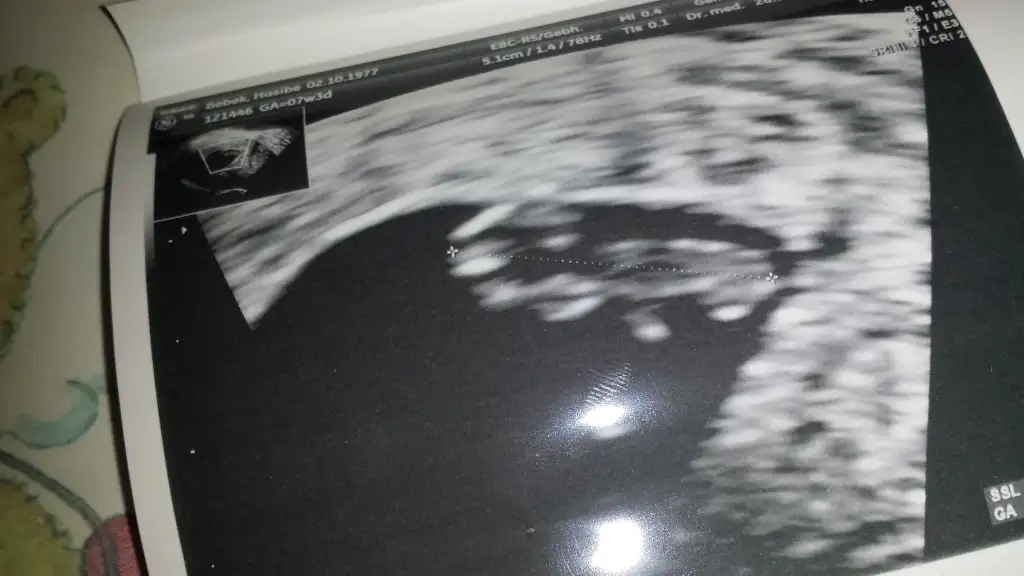

Slm kızlar bugün doktor randevum vardı çok şükür bebegi ve kalp atışını gördük.en son 9 ekimde Türkiyede gitmiştim 4 hafta 3 günlüktü o zaman.Şimdi 7.3 günlük Allahım devamını yaşamayıda nasibetsin bana ve isteyen bütün annelere inşaallahEki Görüntüle 1670444